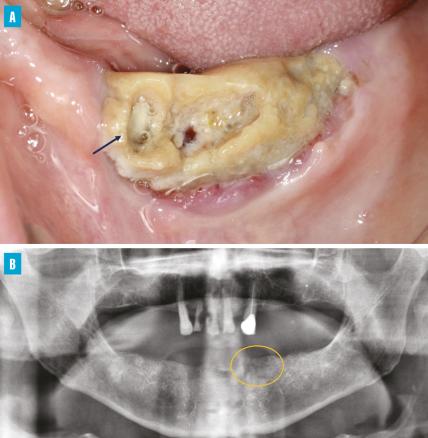

Ostéonécrose de stade 2 au niveau du site extractionnel de la canine mandibulaire gauche chez une patiente ayant reçu un traitement sous-cutané par dénosumab, dans un contexte de cancer du sein avec métastases osseuses.

B. Cliché panoramique montrant une image ostéolytique mal délimitée au niveau du site extractionnel de la canine mandibulaire gauche et un mauvais état des dents maxillaires restantes (lésions carieuses étendues et atteinte du parodonte).